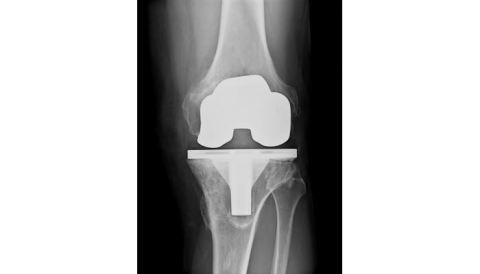

Case Study: Total Knee Replacement Patient with Wound Dehiscence Due to Lymphedema

Managing Wound Dehiscence with Chronic Lymphedema

Patient L entered our facility from an acute care hospital. She had already failed discharge home and arrived with a diagnosis of incision and drainage of her infected knee replacement with heavy wound drainage. She required more than one dressing change per day (even with wicking ultra-absorbent dressings). Her topical dressing was changed to a post-op negative pressure wound therapy (NPWT) dressing at 125mmHg continuous. The dressing was applied in a partially flexed position to allow range of motion (ROM) exercises. Output required changing the 300ml canister BID. Her comorbid diagnosis of chronic lymphedema was obviously slowing the healing of her surgical incision such that even the NPWT pump could not keep up with it. Her physicians cleared her for Manual Lymphatic Drainage (MLD) and multilayer compression bandaging when an ABI showed adequate arterial circulation.